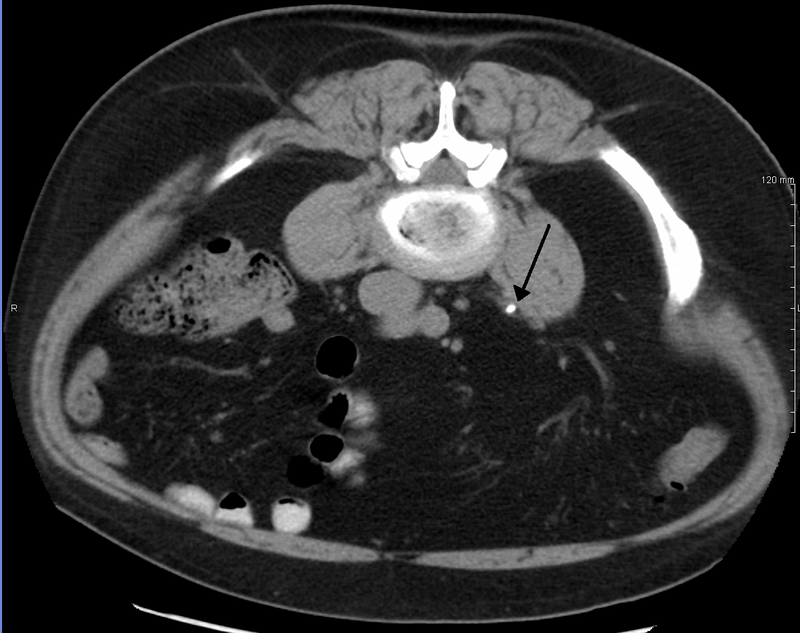

Nephrolithiasis

Nephrolithiasis is the formation of a stone from a urine solute.

Risk factors for nephrolithiasis include:

- Low urine volume

- High solute concentration in the urinary filtrate

Nephrolithiasis presents as:

- Colicky pain

- Hematuria

- Tenderness on one flank

Stone(s) normally passes within a few hours.

If the stone does not pass by itself, medical or surgical intervention may be necessary.